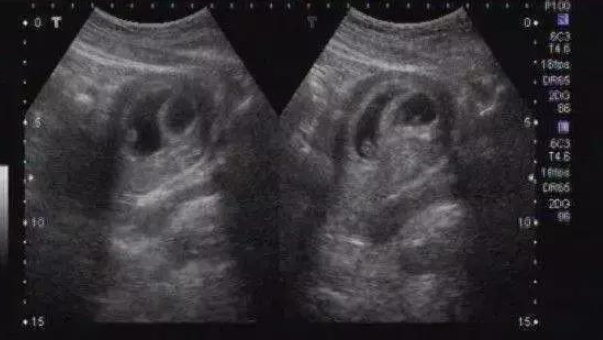

對(duì)于生男生女,是在知道懷孕以后,一直不停歇的話題,其中,通過孕囊數(shù)據(jù)判別胎兒性別也是民間的一種說法,孕囊數(shù)據(jù)看男女怎么看呢?接下來八寶網(wǎng)小編就來說一說。

超聲看到的是形態(tài)上的影像,當(dāng)胎兒的外生殖器長到可以通過超聲看到的程度,就可以進(jìn)行檢查了,一般需要懷孕3-4月以后了,不過誤差也比較大。